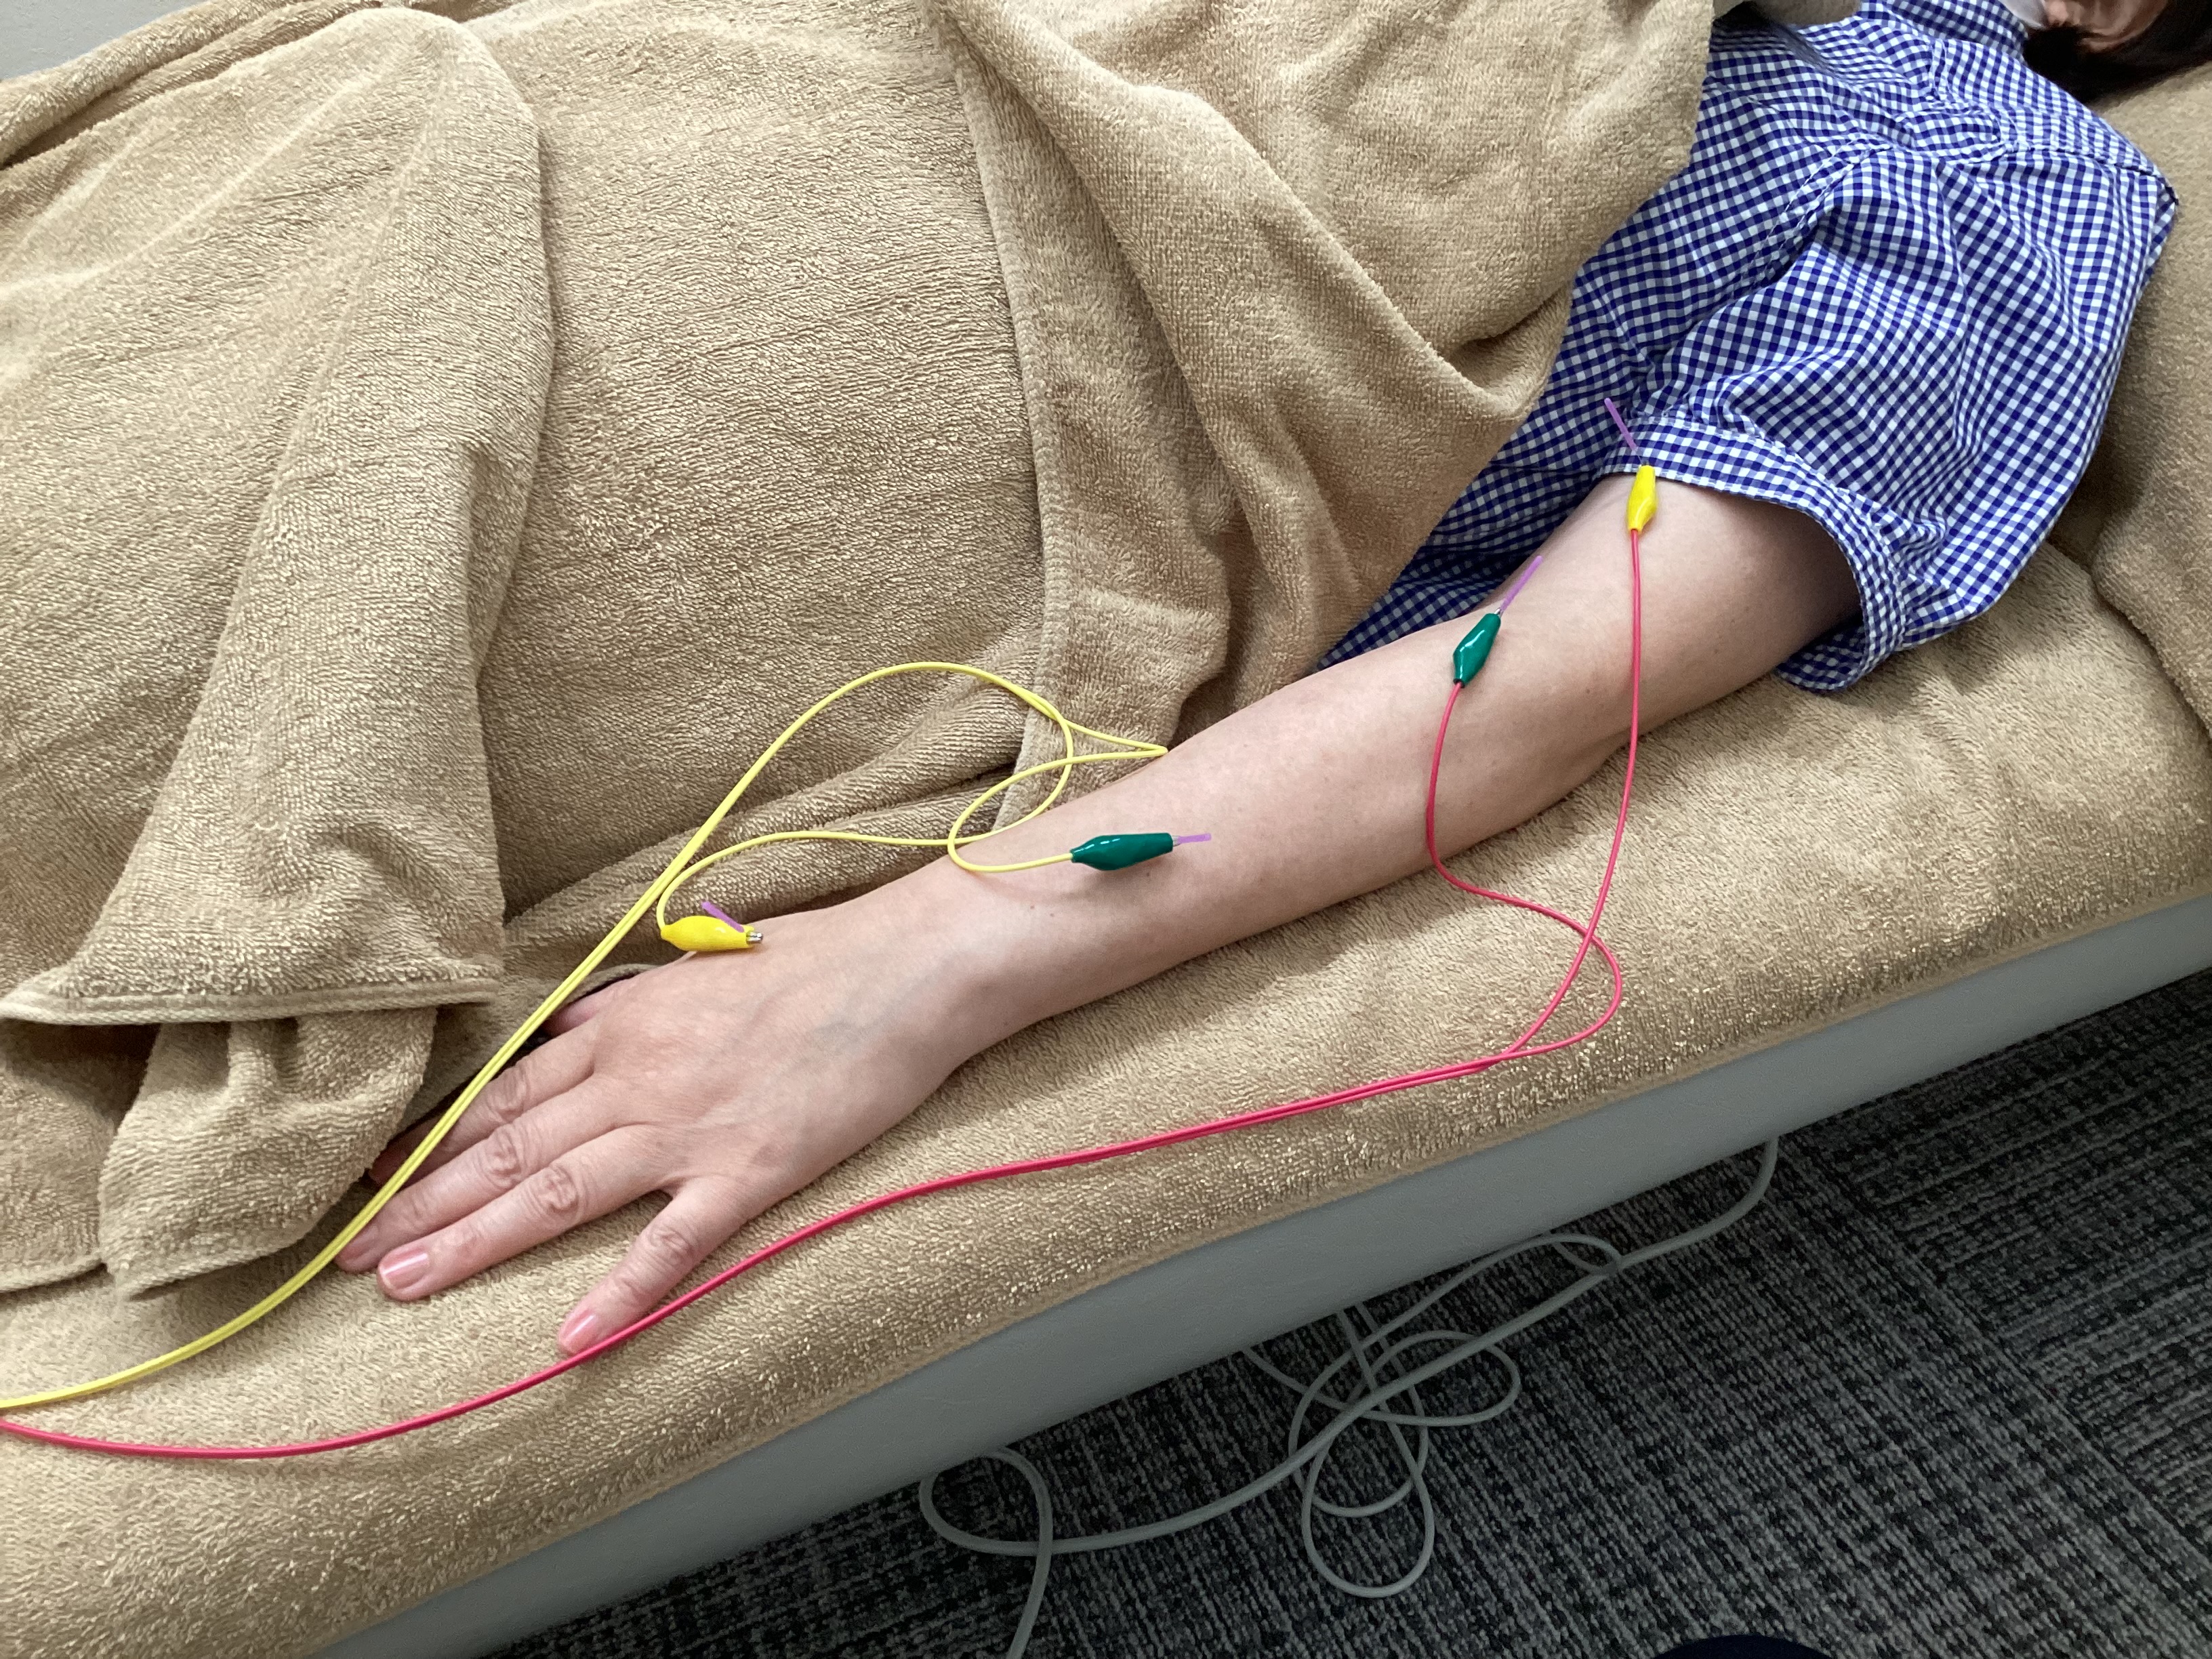

当施設は、国家資格をもったリハビリ専門職と鍼灸師が在籍 した自費リハビリ施設です。経験豊富なスタッフが脳卒中、整形疾患、神経疾患などのリハビリ、お子さんの発達のサポート をします。リハビリ後は症状の原因や今後の施術方針、自主リ ハビリをご説明させていただきます。また140m²の広く清潔な 施設で、リハビリ、鍼灸をお受けいただけます。もちろん感染 対策もしっかり行っていますので、安心してお越しください。

自費リハビリを中⼼に、鍼灸とご家族向けのレクチャーも⾏っています。

ご利用者様それぞれのお困りごとやお悩みを聞き、症状にあった施術プランを提案、実施しています。